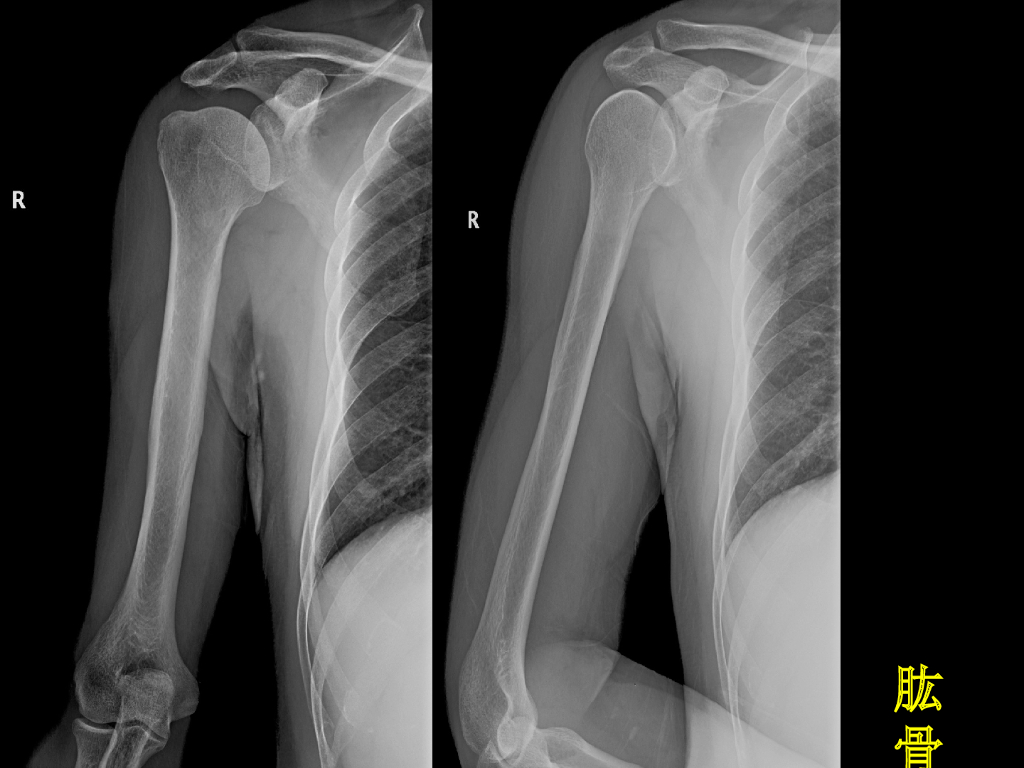

《放射诊断学》演示文稿-骨关节影像学检查与先天性畸形实习课.pdf